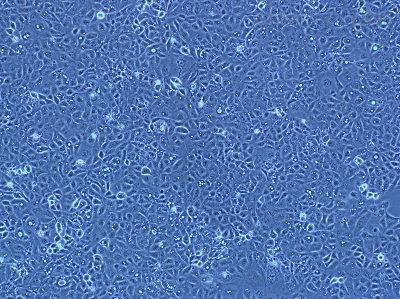

| 细胞英文(简称) | rmc-1 |

| 细胞名称 | rmc-1鼠视网膜muller细胞 |

| 细胞形态 | 贴壁 |

| 细胞活力 | 95%(Viability by Trypan Blue Exclusion) |

| 培养条件 | RPMI-1640 +10% FBS;37℃,5% CO2 |

| 传代方法 | 建议1:2-1:3 两天换液一次 |